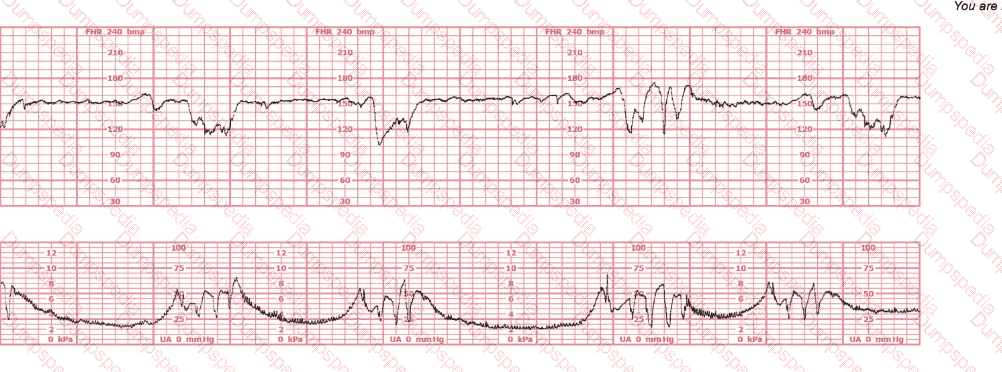

This is a tracing of a multiparous woman in the second stage of labor. The vertex is at +3 station. This pattern has continued for the last 20 minutes. She has been pushing for 2½ hours, and oxytocin is infusing at 12 milliunits/minute. Management should include